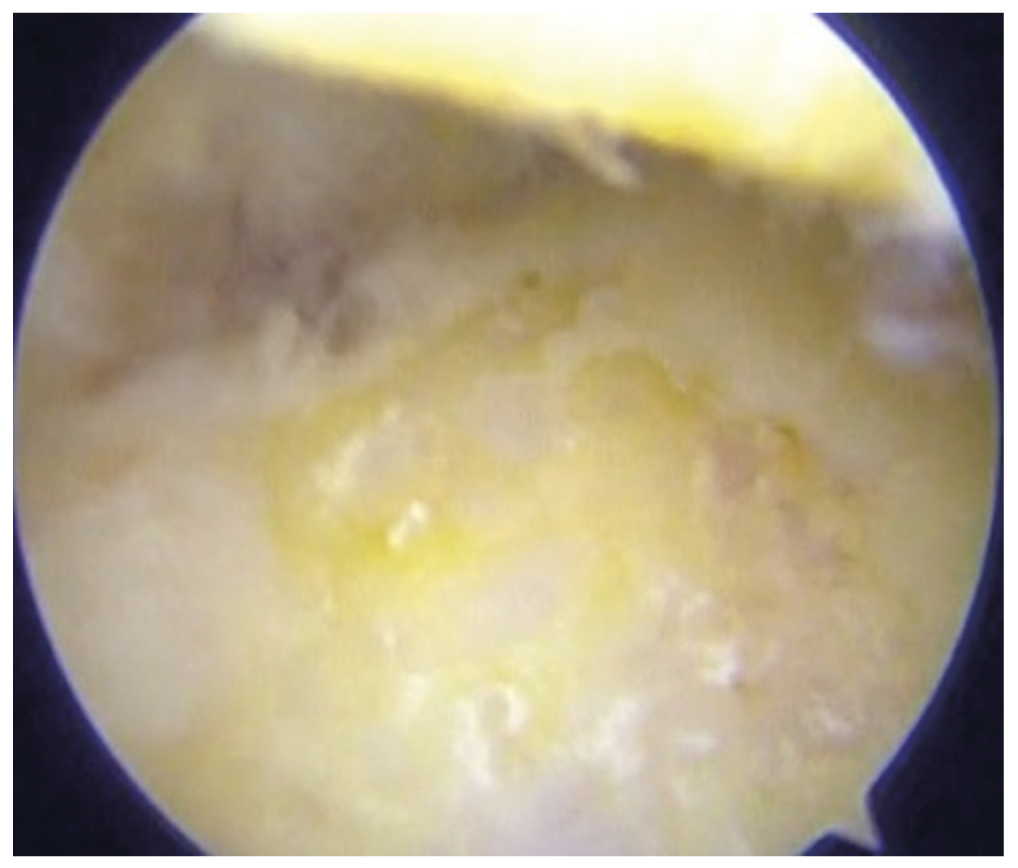

Patient No. 2 had a significant collapse of the talus bone with incorrectly consolidated subtalar arthrodesis and a varus deformity of the lower limb axis, which are prognostically unfavorable in the treatment when using the distraction arthroplasty of the ankle joint. Before surgical treatment, there were visible grade IV foci of cartilage defects (Outerbridge) (Fig. 5). In 12 months after the distraction arthroplasty of the ankle joint, due to the recurrence of the anterior impingement-syndrome and repeated formation of osteophytes in the anterior segment, repeated arthroscopy was done. The visualized findings included the coverage of the defect areas with the cartilage-like tissue, showing the grade II–III of the Outerbridge classification (Fig. 6). Similar findings were observed in patients No. 3 and No. 4.

Рис. 6. Patient’s No. 2 talus 12 months after ankle distraction arthroplasty with signs of regeneration of cartilage tissue.